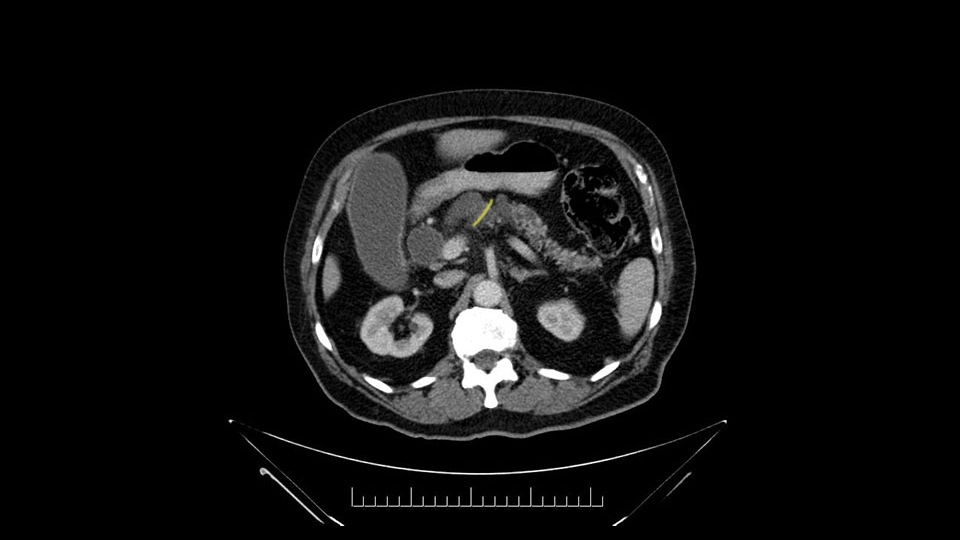

The next item that I would look at: the issue would be the vessels and usually start at the portal vein, watch the portal vein, follow it down, down-down-down to the neck of the pancreas - which is here - and there’s no impingement by tumor, which is great. The SMV and the splenic vein, which is here. The splenic vein junction is normal, which is great.

Then either through the coronal or the axial, I’ll do both. Look at the SMA -which is here- I had already looked at it and I don’t see any involvement. There’s the SMA with a nice fat plane between the SMA and the tumor. Over here you can see on the axial, there’s the SMA. Everything on the right side of the SMA has got some nice black around it, which is fat, which means probably no tumor [no tumor, no tumor]. Follow it up to the origin, coming off the aorta. So those are the two technical things that I worry about: the SMA and the SMV.

The next thing we always evaluate, although we do not expect invasion to the portal veins in this case, we must always trace the path of the portal vein, in both directions, from top to bottom. The splenoportal confluence and the superior mesenteric vein, which in this case does not appear to be compromised.

Por otro lado, siempre evaluamos -aunque en este caso no esperamos que haya invasión de los vasos portales-, siempre hay que hacer el recorrido de la vena porta, en ambos sentidos, de arriba hacia abajo; el confluente esplenoportal y la vena mesentérica superior, que en este caso no aparentan estar comprometidos.